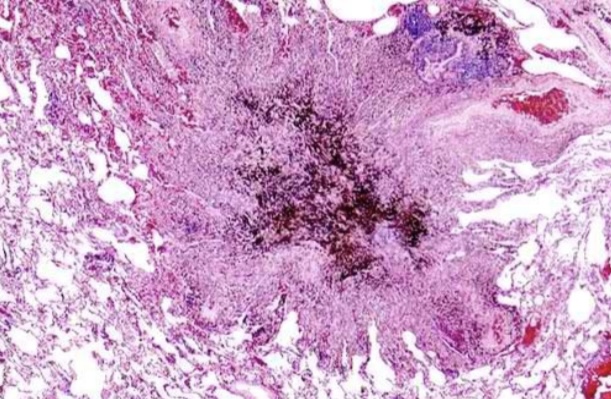

Anthracosis

Asbestosis

Chalicosis

Pneumoconiosis

Silicosis